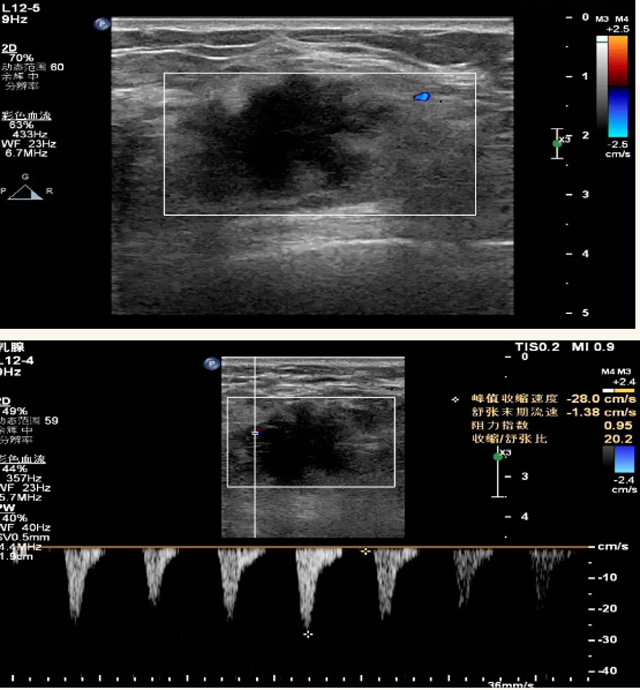

乳腺B超检查无辐射,对囊性病变敏感,可以实时观察病灶。超声引导活检跟手术前的定位。就是它对于微小的钙化查出率比钼靶稍微差点。磁共振MRI检查也是是没有辐射的,对备孕跟已经怀孕的人士比较友好。不用担心这个辐射影响胎儿问题。对乳腺病灶敏感性较高,致密乳腺病灶、乳腺癌的复发,准确鉴别囊性及实性病变。可以帮助临床医生判断恶性、良性病变。但是MRI磁共振对微小钙化不明显,微钙化还是钼靶靠谱点。检查时间比较长,有伪影的影响。费用相对B超,钼靶高很多。